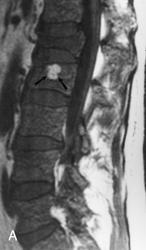

ГМ. СМ. Миеломная болезнь (множественная плазмоцитома). +

Миеломная болезнь (множественная плазмоцитома).

Лия А. Moulopoulos и Мелетий А. Dimopoulos